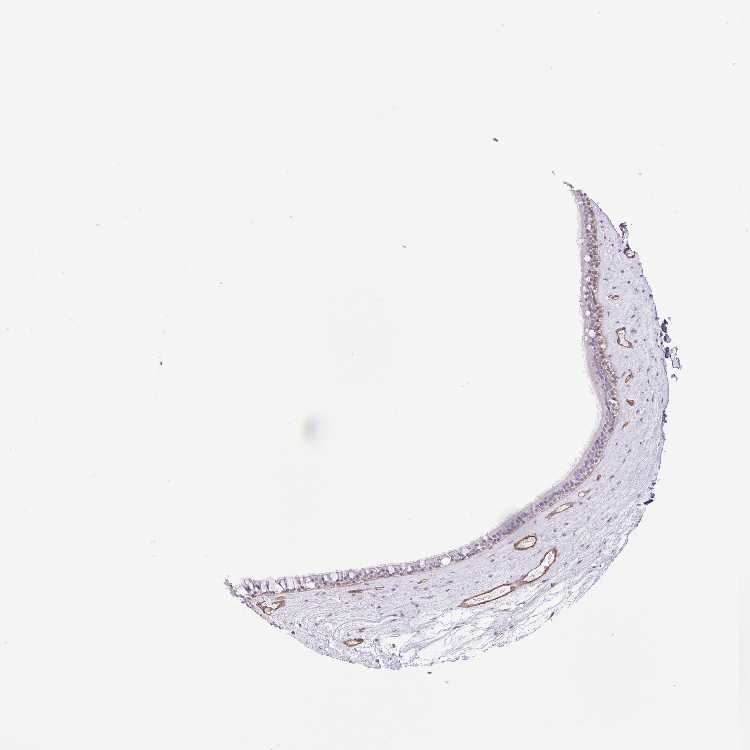

NASOPHARYNX - Antibody stainingi

Antibody staining in the annotated cell types in the current human tissue is reported as not detected, low, medium, or high, based on conventional immunohistochemistry profiling in selected tissues. This score is based on the combination of the staining intensity and fraction of stained cells.

Each image is clickable and will lead to virtual microscopy that enables deeper exploration of all samples and also displays staining intensity scores, fraction scores and subcellular localization as well as patient and tissue information for each sample.

Antibody HPA036124Antibody HPA036125Antibody HPA064821

Respiratory epithelial cells Not detectedNot detectedNot detected